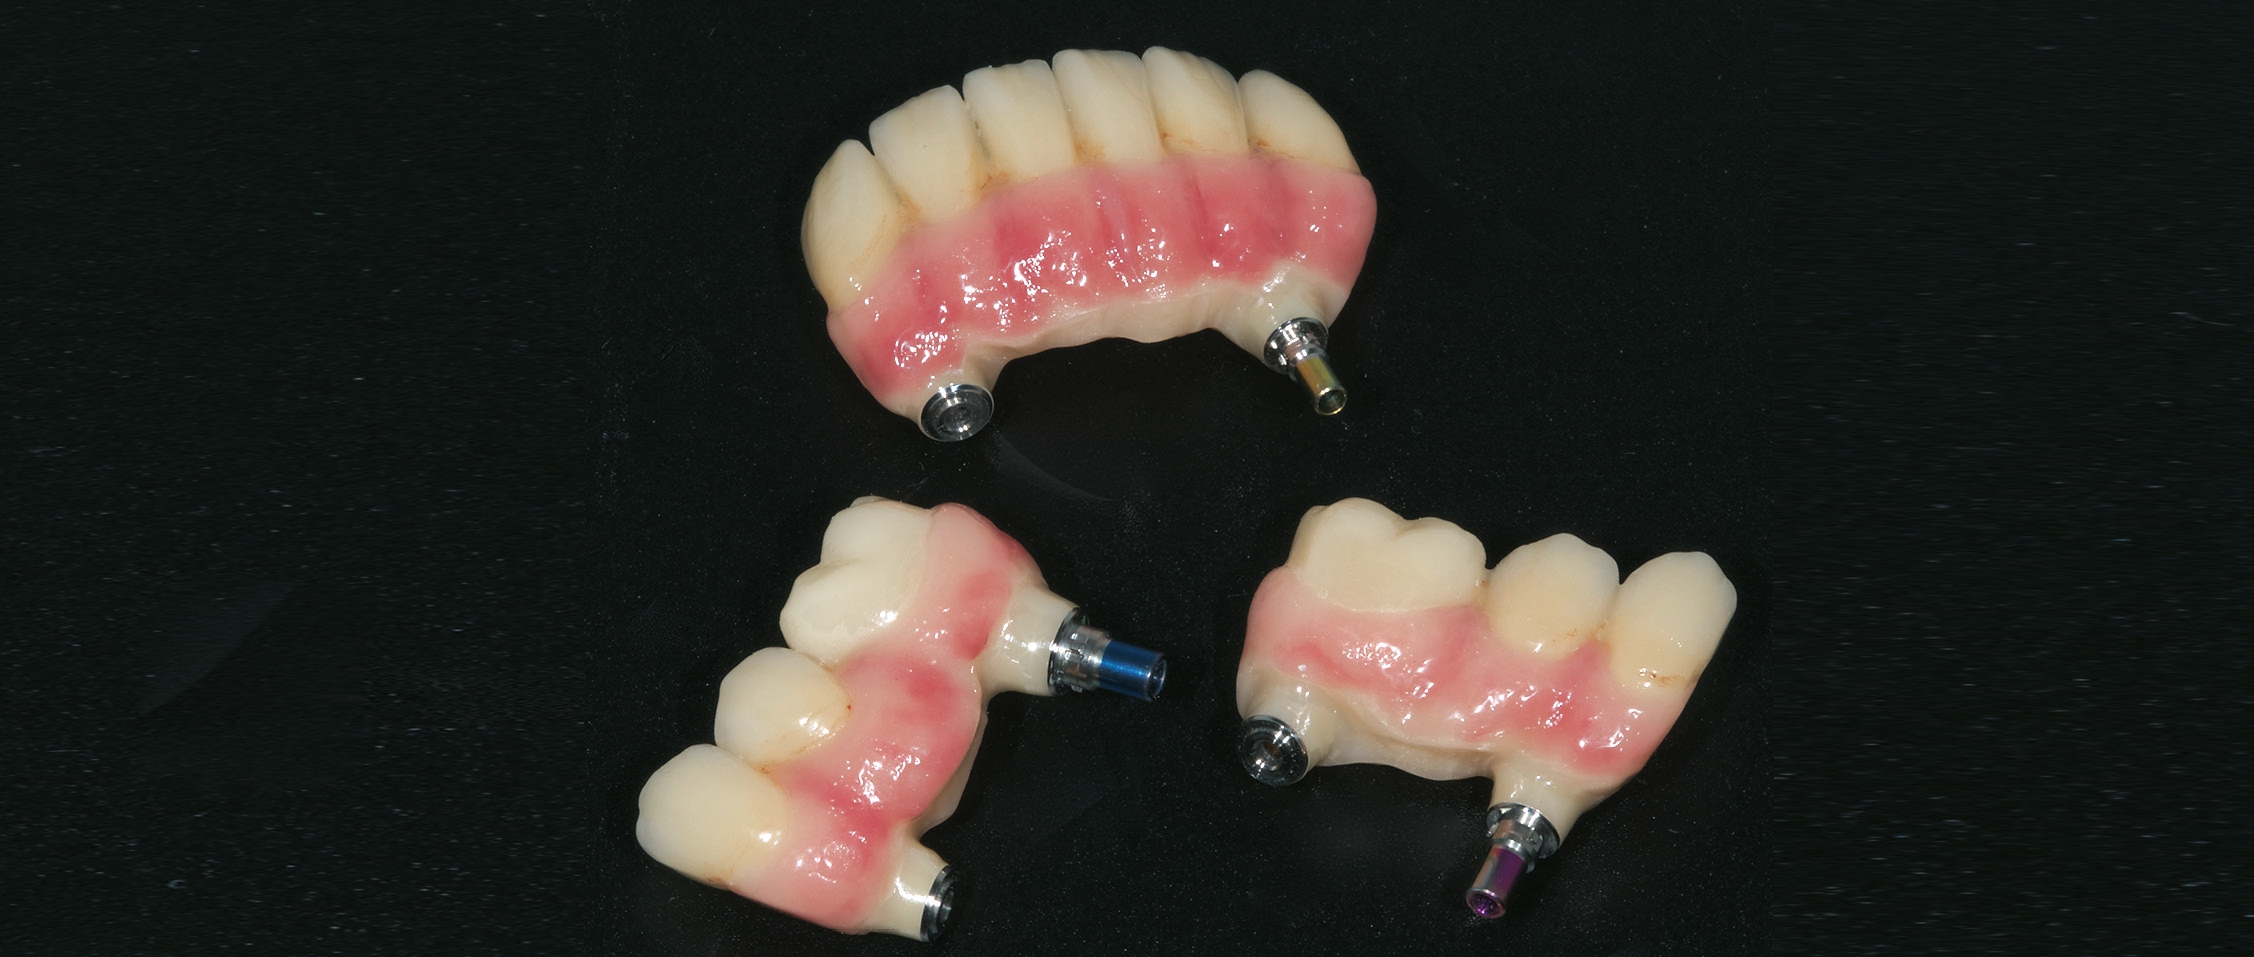

Bei reizlosem postoperativem Verlauf konnten die Implantate wie geplant nach drei Monaten freigelegt werden. Um das Emergenzprofil für die Prothetik möglichst optimal zu gestalten, kamen dabei sowohl zylindrische als auch wide body Gingivaformer zum Einsatz. Nach einer Heilungszeit von zwei Wochen für das Weichgewebe wurde der Patient für die prothetische Phase an die zuweisende Zahnarztpraxis (Dr. Andreas Karg, Lenggries) zurücküberwiesen. Dort wurde der Unterkiefer mit drei Brückensegmenten 46-44, 43-33, 34-46 definitiv versorgt. Zunächst erfolgte nochmals eine exakte zentrische Relationsbestimmung mit auf den Implantaten verschraubten Gerber-Stützstiftregistrat-Platten (Abb. 16). Anschließend wurden die Brückengerüste in CAD/CAM-Technik konstruiert und aus Zirkonoxid gefräst und individuell keramisch vollverblendet. Im Oberkiefer wurde zunächst ein auf provisorischen Abutments reversibel zementiertes Langzeitprovisorium aus PMMA mit glasfaserverstärkten Strängen (Targis Vectris) eingegliedert, um Phonetik, Ästhetik, Hygienefähigkeit und die Bisslage nochmals über eine Tragezeit von sechs bis neun Monaten zu evaluieren und falls notwendig letzte Korrekturen durchführen zu können (Abb.17-23). Danach ist die definitive Versorgung mit vier einzelnen Brückensegmenten in regio 16- 14, 13-11, 21-23 sowie 24-26 geplant.

Das implantatprothetische Konzept mit acht Oberkieferund sechs Unterkieferimplantaten wurde gewählt, um große Brückenspannen zu vermeiden. Durch die Implantatposition sind im Oberkiefer vier und im Unterkiefer drei jeweils kurzspannige Brücken realisierbar (16-14, 13-11, 21-23, 24-26, 36-34, 33-43, 44-46). Dies bringt Vorzüge hinsichtlich der Zahnersatz-Passung einerseits, erhöht aber auch die Reparaturfreundlichkeit im Falle eines Chippings o.ä. signifikant.